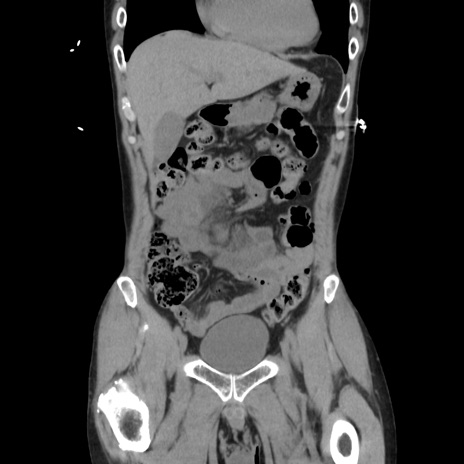

症例37(冠状断像)

【症例】40歳代 男性

【主訴】腹痛

【現病歴】4時間ほど前に電車に乗車中に臍部上より腹痛出現。徐々に増悪し起立困難となり、救急外来受診。生ものは数日食べていない。今朝お雑煮を食べた。

【身体所見】BT 36.8℃、BP 117/84mmHg、HR 91/min、SpO2 97%、苦悶様、腹部:臍上部広範囲圧痛あり、反跳痛±

【データ】WBC 8100、CRP 0.03